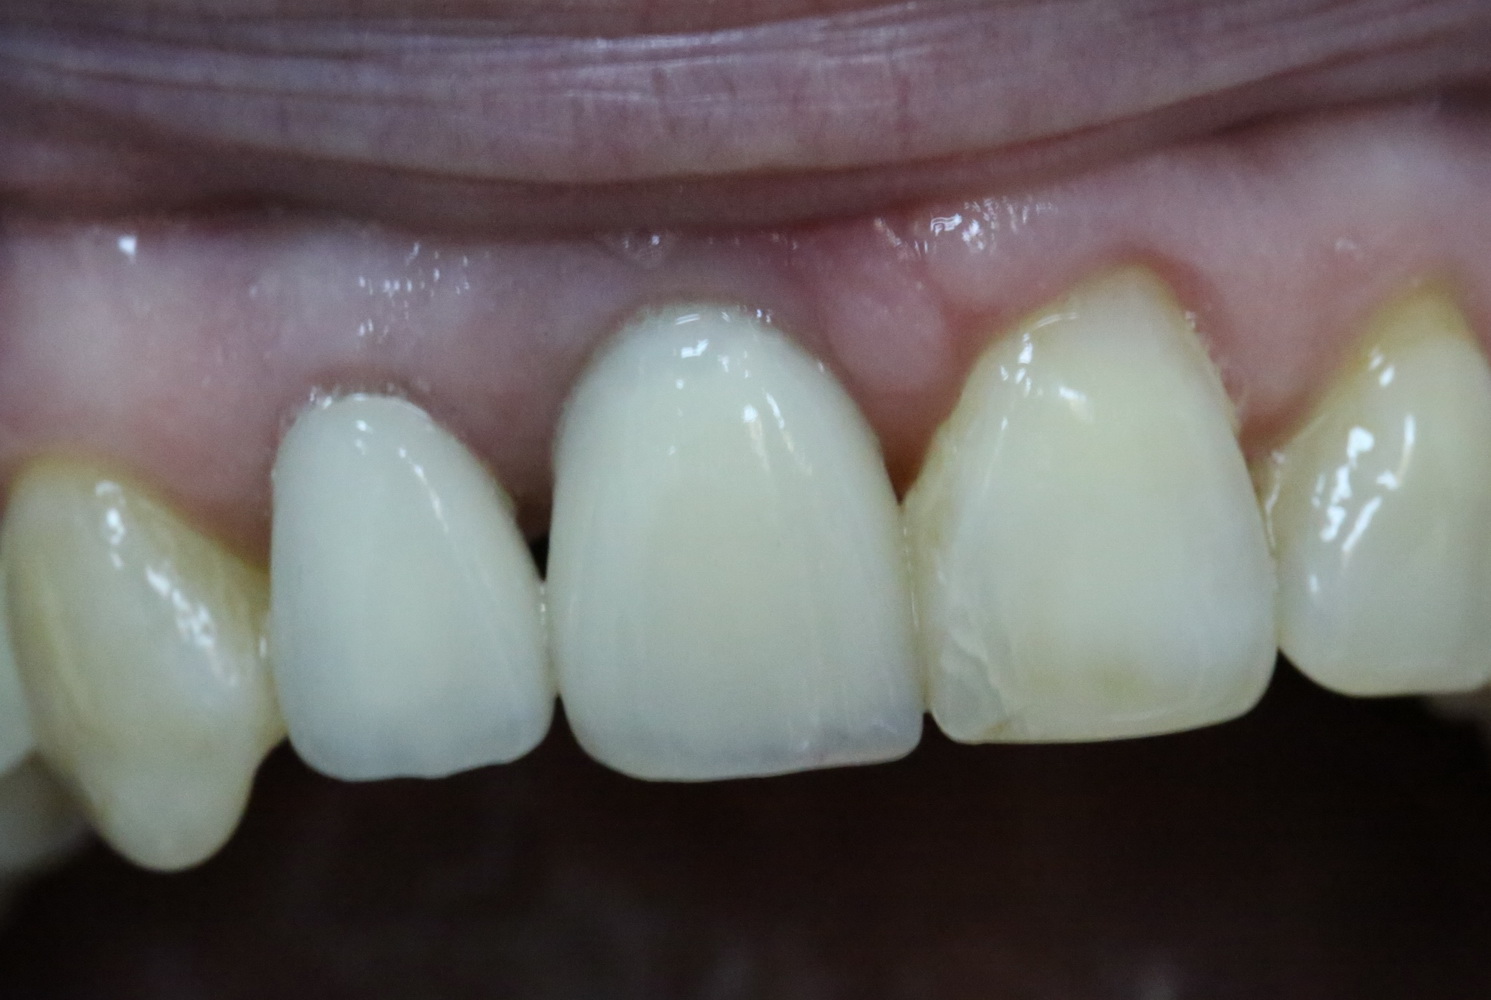

Немедленная имплантация — оптимальное решение в любой клинической ситуации